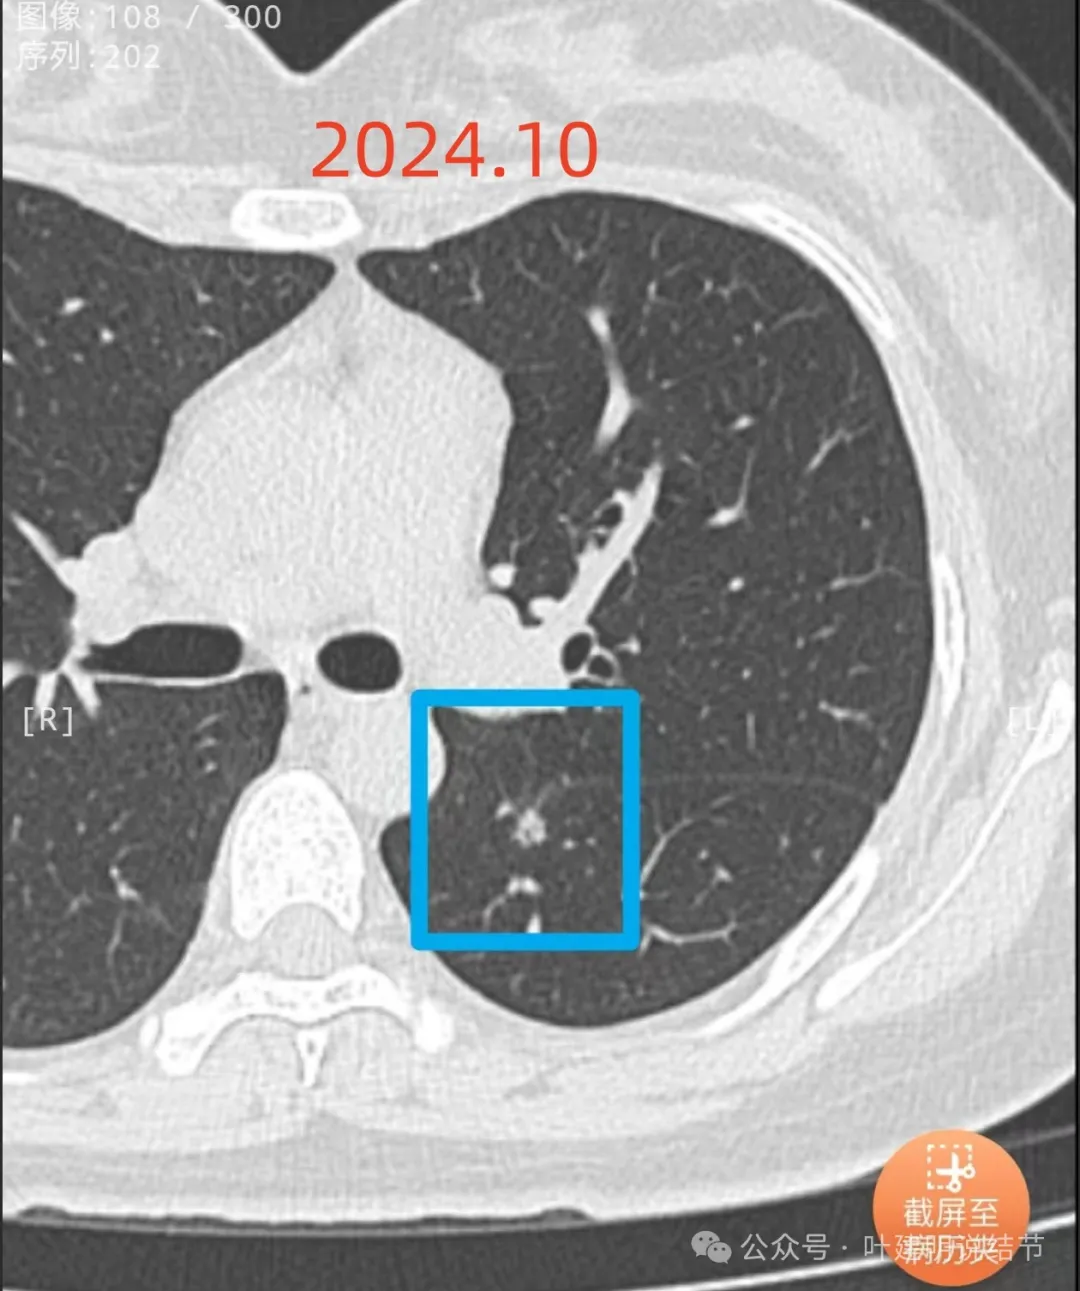

先看不同时间段最明显层面的影像:

2024年10月复查仍无明显进展,表面不平,叶间裂有所牵拉。

病灶现出,密度较高,贴着叶间裂。

叶间裂有牵拉,有微小血管进入病灶,灶内有小空泡征,密度整体显得较高,轮廓清楚,瘤肺边界清。

表面有小棘突或毛刺样征,密度显得杂乱。

轮廓清,小空泡征明显,密度较高,基本上是实性。

边缘区密度较淡。

冠状位实性位小空泡征的样子,与叶间裂之间有小条状相连,整体轮廓较清,空泡壁厚薄不均。

矢状位沿着叶间裂略显长条状,靠叶间裂侧密度较高,边上的低密度管道状像细支气管,横断面的上小空泡是扩张的细支气管吗?矢状位上看收缩力不明显。

左下叶背段小结节,虽然较小,但密度不低,大部分是实性成分,且表面不光滑有小棘突状、邻近叶间裂,并有细条状连到叶间裂,中间有小空泡状,随访持续存在,虽然矢状位上看不太像恶性,但综合考虑仍是肿瘤性质的可能性大。对比各次病灶本向说不上显著变化,但我的意见倾向近期找时间单孔胸腔镜下局部切了为妥,原因如下:1、性质考虑恶性,而这种实性占比较多且表面不平的,容易是浸润性腺癌腺泡或乳头型,微浸润性腺癌或原位癌的可能性小些;2、冠状位与矢状位上看,病灶紧贴叶间裂,这种实性成分的早期肺癌贴着胸膜是存在一定风险的;3、位置在边上,能楔形切除,肺功能损失少,手术风险小,恢复快,去除病灶不单是明确诊断,还是有效的治疗手段;4、随访到明显进展,切除的范围相对可能要考虑更多一点,那这种推迟手术并不划算;5、实性为主密度的,即使仍随访,也等不了太久,但风险却有增加,权衡之后随访是不划算的。意见供参考!